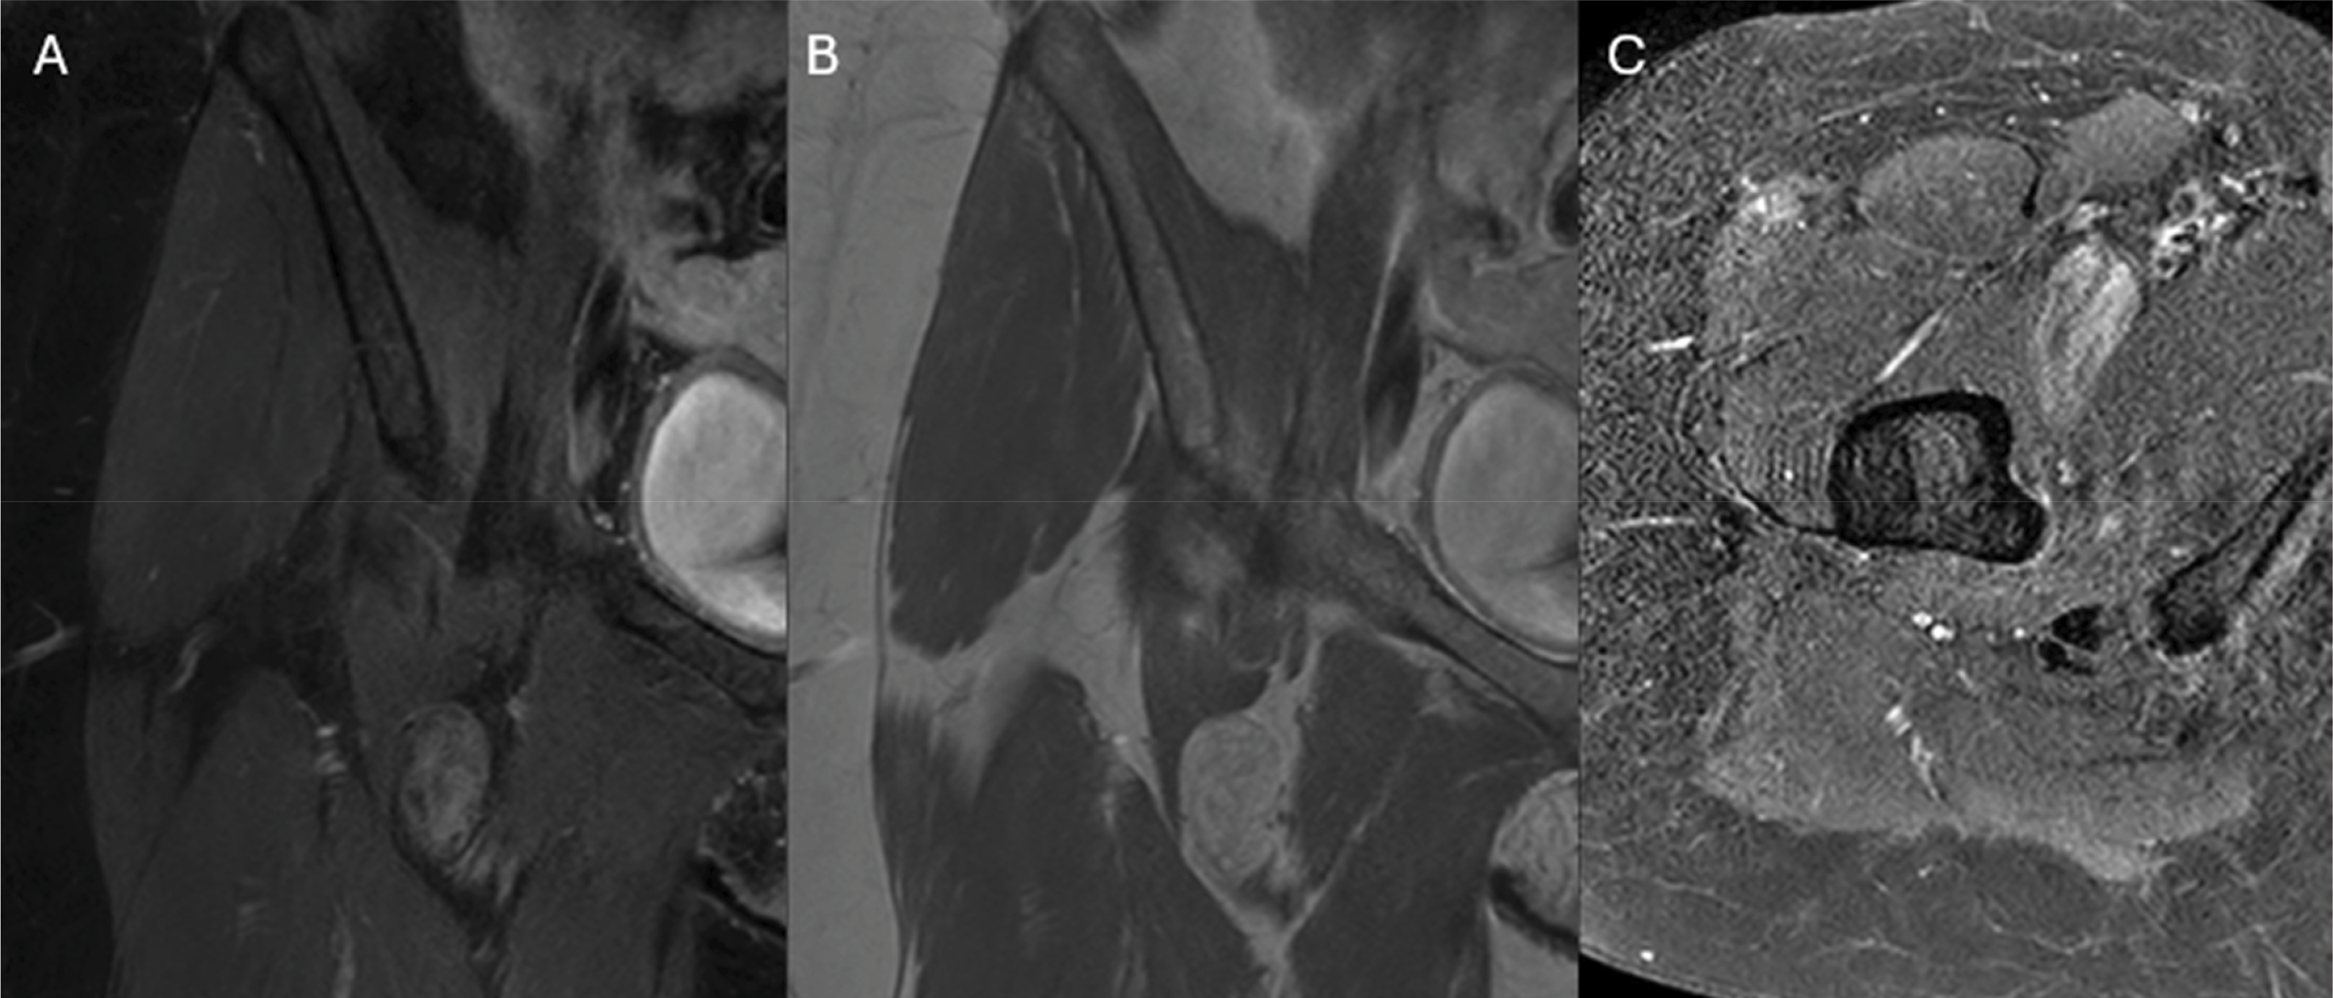

Coronal contrast‑enhanced T1 Dixon images (Figure 3A and B) and axial T1 spectral presaturation with inversion recovery (SPIR, Figure 3C) imaging demonstrated enhancement of these regions of (remnants of) low adipose tissue without involvement of the adjacent structures.

Figure 3

Coronal post‑contrast enhanced images (A and B) and axial post‑contrast SPIR images demonstrate enhancement of the regions of low fat‑content.